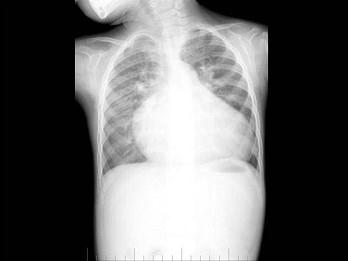

问题 男性,1岁零8个月,生长发育差,易患呼吸道感染,心悸气促,行心脏正、侧位片检查如图所示,错误的是 ( )

选项 A、房间隔缺损 B、室间隔缺损 C、肺纹理增多 D、侧位示心前间隙变窄,心后食管前三角间隙消失 E、正位示心影向两侧扩大,心尖左移

答案 A